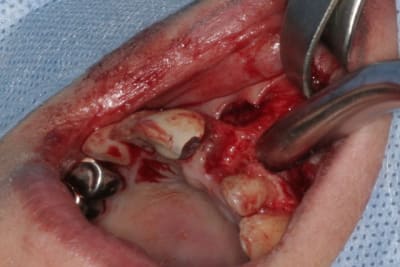

tien, ce matin, extraction de 24/25, curetage méticuleux, forage, comblement du gap, pose des 2 implants qui se sont bloqués à 50Ncm au CA sur les 3 ou 4 mm apicaux, pose des vis de cicat, sutures...35min....tranquille...

un autre cas EII MCI sur 11/21...mais en photos (j'ai aussi la vidéo, faut que je la passe sur youtube)

Voilà ce que l'on arrive à faire mais ce fut limite!